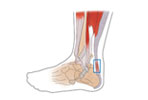

¹ß¸ñÀÎ´ë ¼Õ»ó

¾ÆÅ³·¹½º°Ç¿°